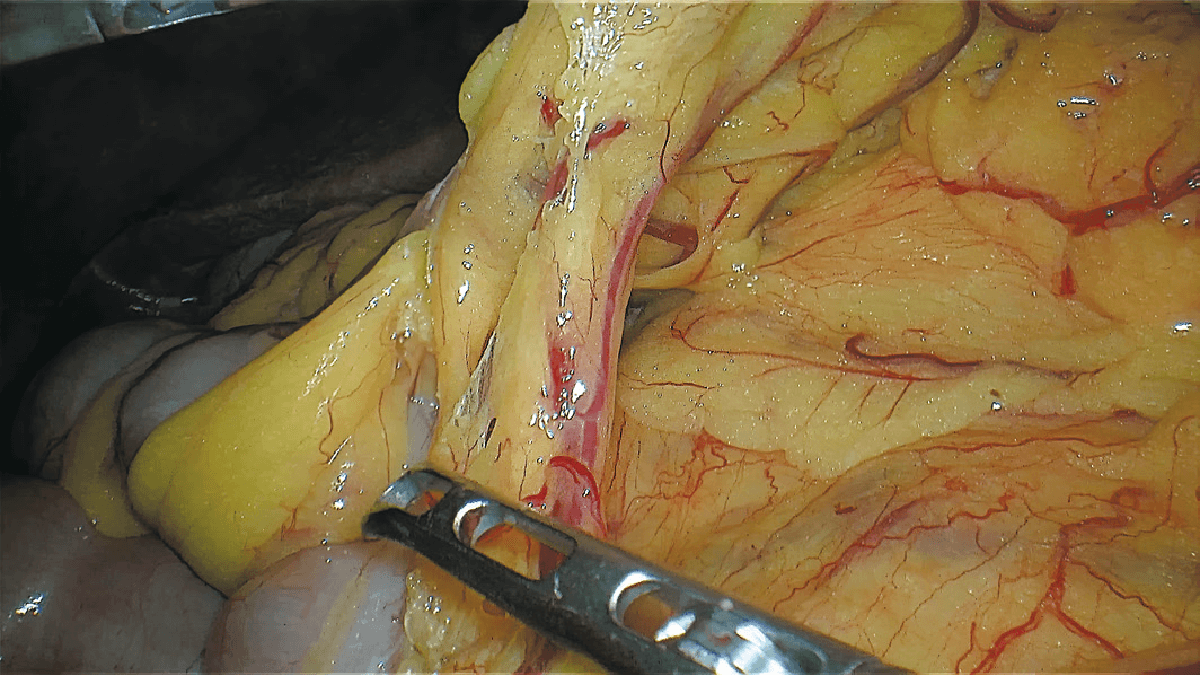

表面细节不遮盖

边界清晰,利于切缘评估

细微结构无伪影

避免术中误伤

荧光信号强弱分明

精准辅助临床决策

术中实时多维导航,领航诊疗一体新标准